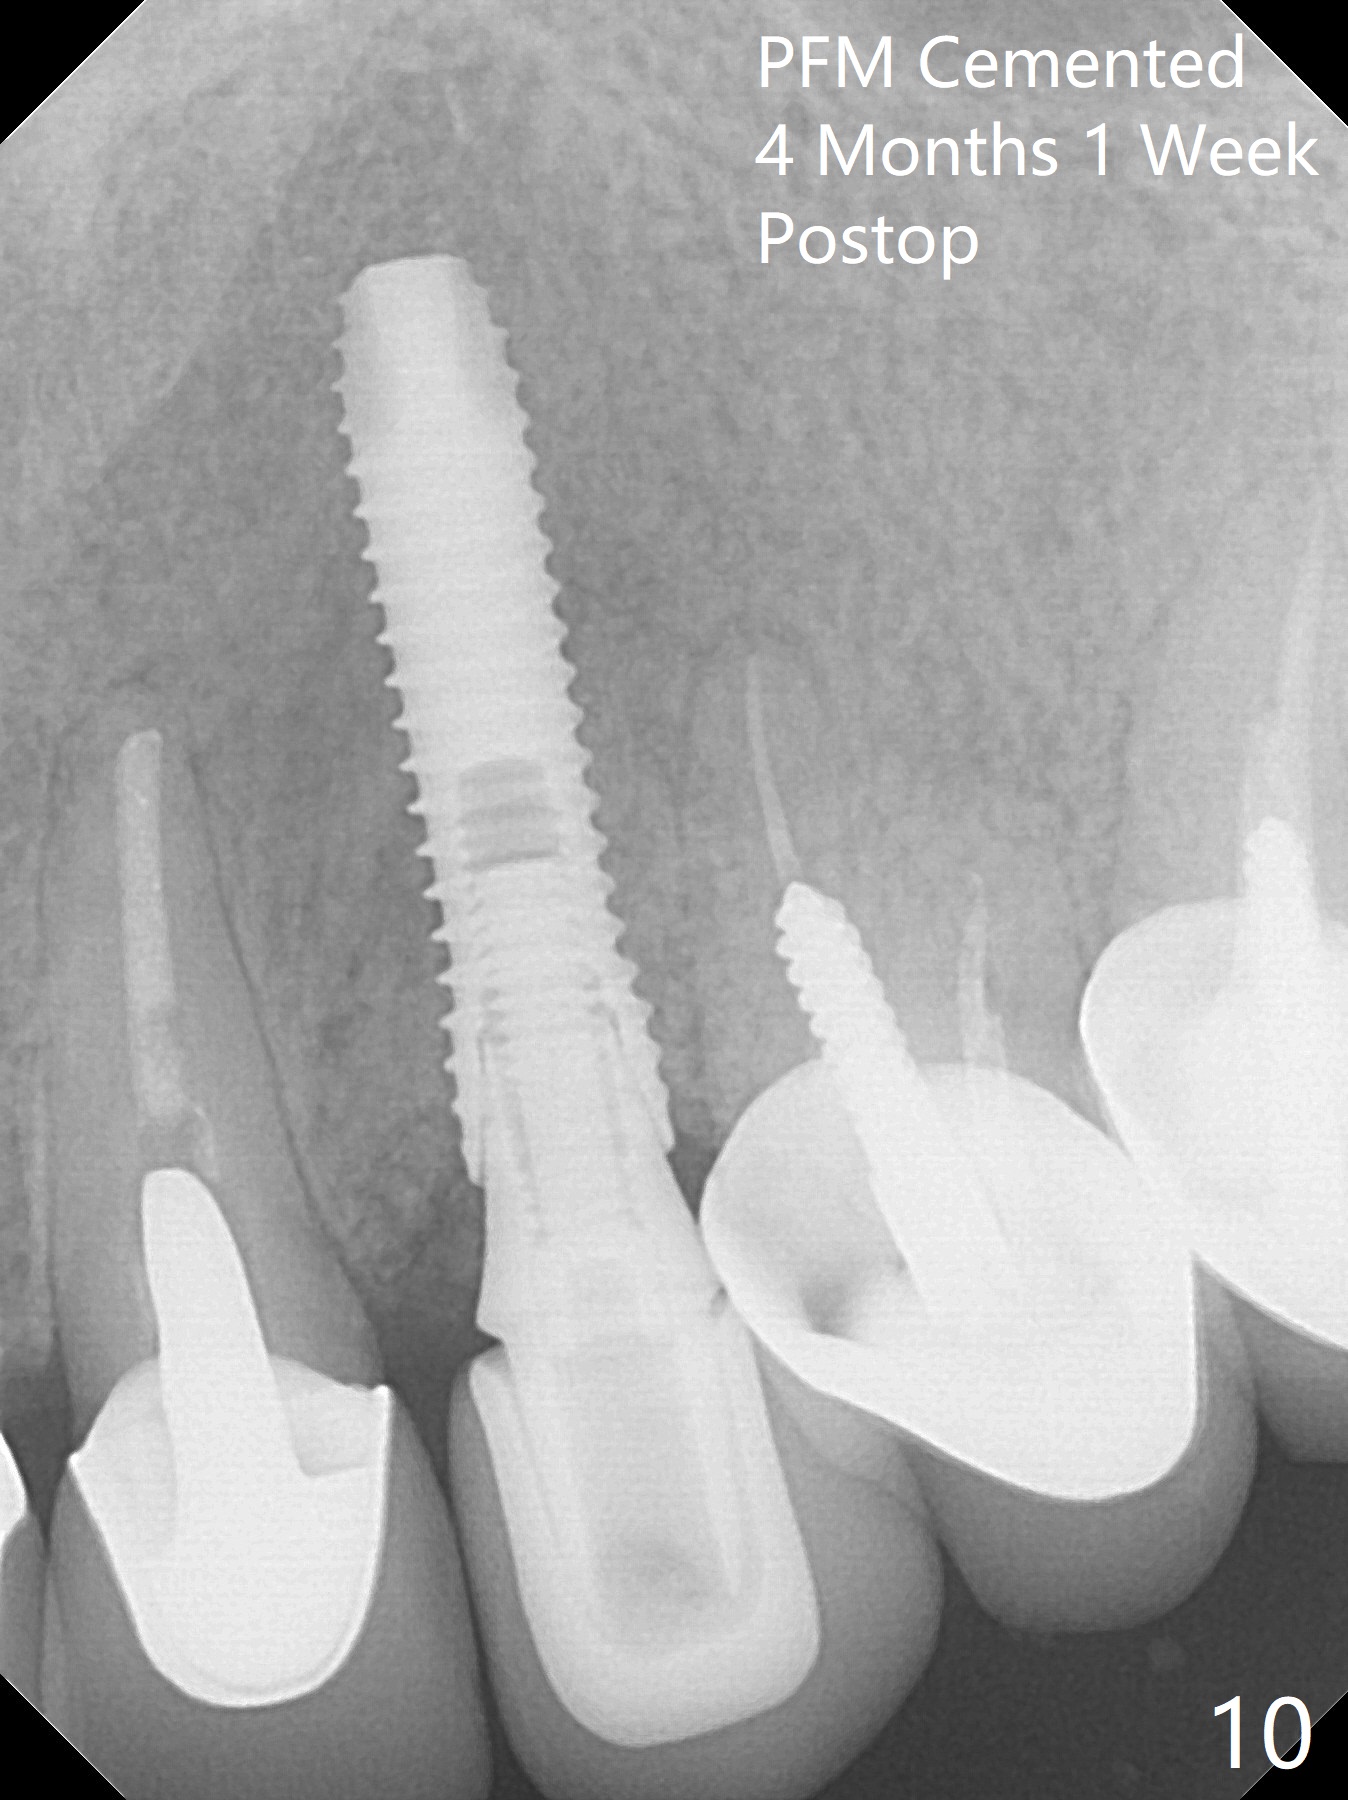

In spite of severe apical infection (Fig1,2 *), a thin narrow strip of the buccal plate (arrowheads, corresponding to the keratinized gingiva) is present when the tooth #11 is extracted. The thin bone keeps the bulging alveolus, i.e., reservoir for bone graft (Vanilla/Osteogen Fig.4 *) after placement of a 3.8x16 mm implant (Fig.3,4). A 4.5x1 mm temporary abutment, placed and trimmed for an immediate provisional, seems to be short in cuff. When an implant is placed deep to prevent periimplantitis, the cuff should be longer, i.e., 3 mm. X-ray should be taken for the depth confirmation after temporary abutment placement. Eight days postop, the mesial gingiva erythema has subsided (Fig.5 < (P: provisional)), while the apical swelling is no longer tender and most likely due to packed bone graft (*). Panoramic X-ray taken 2 weeks postop shows the clearance from the nasal cavity or the maxillary sinus (Fig.6). While the hard tissue around the implant seems to be healthy 5 months postop (Fig.7), the soft tissue is not (Fig.8). The temporary abutment is changed to a cemented one (4.5x5(2) mm) for impression (Fig.8). Since the neighboring crowns are PFM (Fig.6), the new crown will be made of the same material for shade match. Indeed PFM helps shade match in this case as well (Fig.9,10). Switching abutments (from temporary to cemented) makes it difficult to seat the crown. Post cementation X-ray leaves record for future contact loosening. The buccal gingiva remains erythematous associated with open margin (Fig.11 >) 1 year 4 months post cementation. There is no obvious bone loss 1 year 4 months post cementation (Fig.12). It appears that the crown and abutment need to be changed. Although the gingival margin remains erythematous, the gingival hemorrhage is basically lacking due to better oral hygiene during Shelter at Home (1 year 9 months post cementation, Fig.13). Change in abutment and crown will be conducted post coronavirus pandemic. In fact the abutment is incompletely seated (Fig.14 <). In addition, the tooth #12 is symptomatic with PARL associated with the buccal root (*). CBCT indicates possible buccal root fracture (Fig.15,16 ^) and loss of the buccal plate (Fig.16 <).